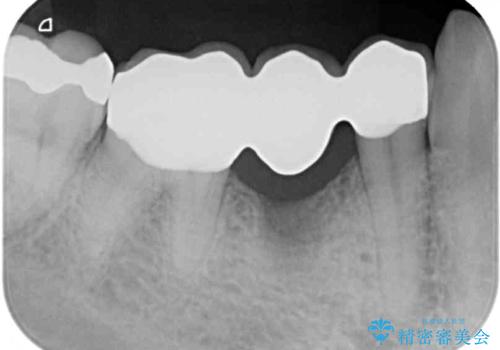

- 近医でむし歯治療をしたものの、術後も痛みが続くとのことで来院された患者様です。

当初は根管治療を再度行うことで痛みが引くことを期待しましたが、該当歯の歯周ポケットが局所的に深くなっていることから、歯に穴が開けられているか破折している可能性が疑われました。

歯肉を開いたところ、周辺の歯槽骨は全て炎症で失われ、破折と同等の穴が開けられていることが分かったため、抜歯を行いフルジルコニアブリッジにて補綴することとしました。